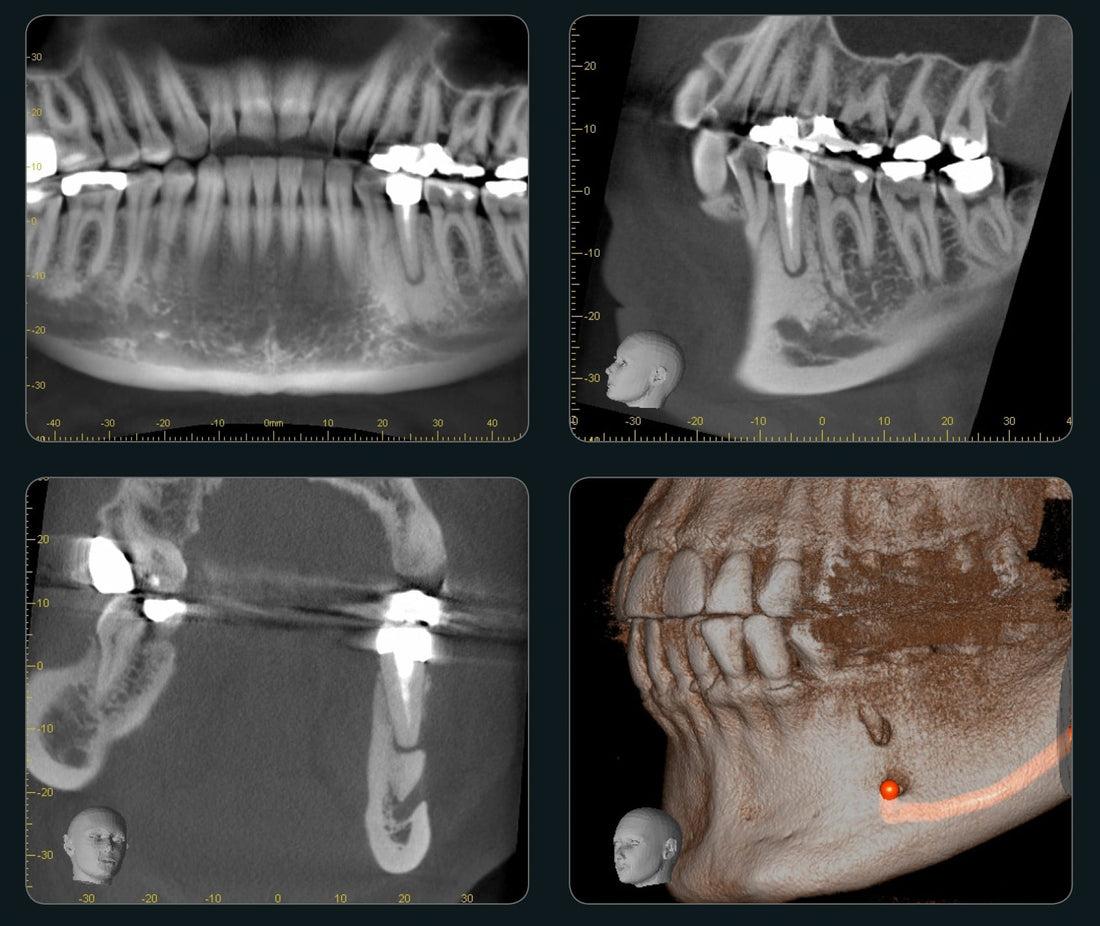

Rising Demand for Dental Imaging: The demand for CBCT in dental imaging is growing rapidly due to the increasing need for accurate 3D imaging for dental surgeries, implants, and orthodontics. CBCT systems provide high-resolution images with lower radiation compared to traditional CT scans, making them ideal for dental practices.

Focus on Preventive Healthcare: Finland places a strong emphasis on preventive healthcare, which includes regular dental check-ups and early detection of dental issues. CBCT systems help in diagnosing oral diseases and planning treatments, further driving demand for these technologies.

Aging Population: With a steadily aging population, Finland is seeing an increased demand for dental treatments such as implants and dentures. CBCT technology is critical for planning these procedures, leading to greater adoption of CBCT systems in the dental field.